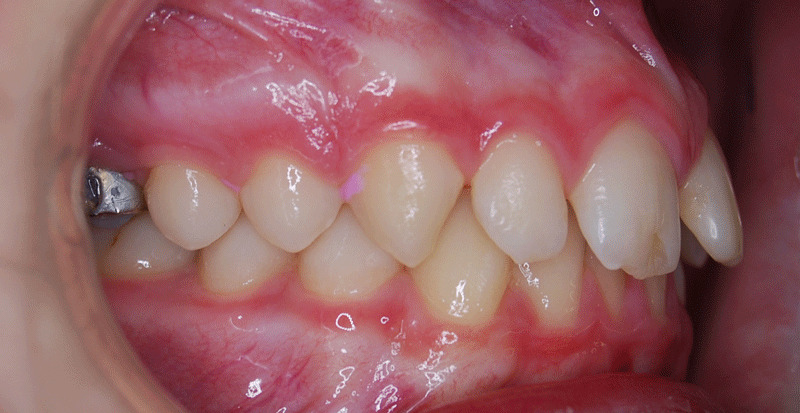

Overbite before and after

Deep bite before and after side view